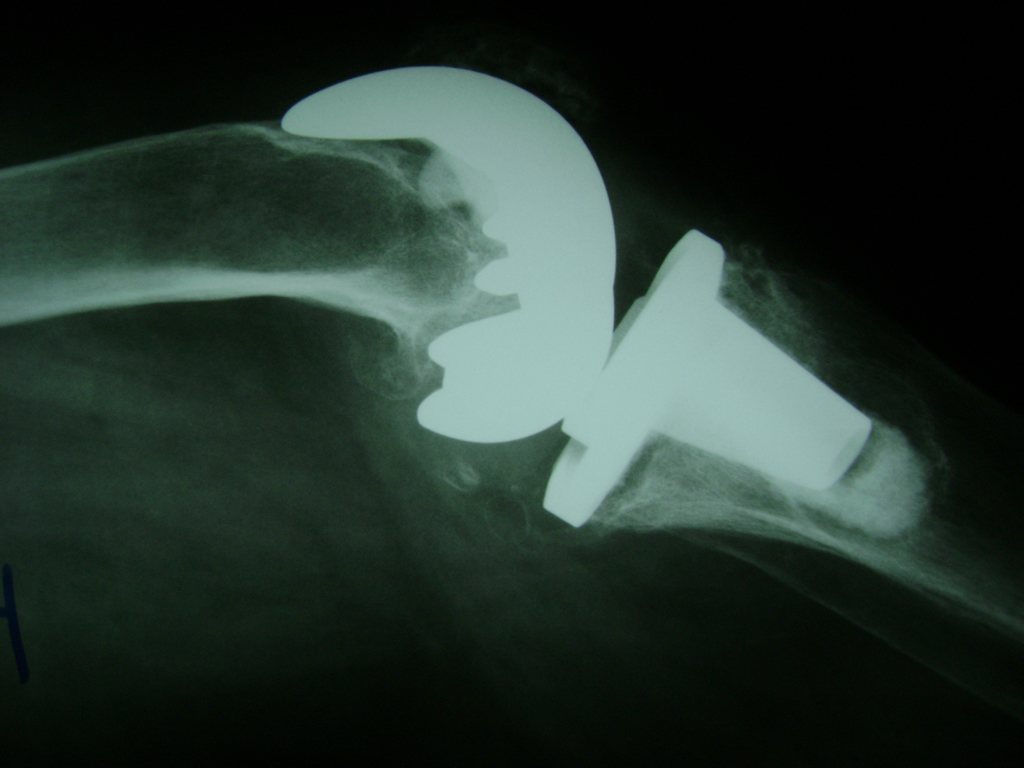

La artroscopia de rodilla es un cirugía en el cual la estructura interna de la articulación es examinada ya sea para realizar un diagnostico o para realizar un tratamiento, este procedimiento se realiza utilizando un instrumento parecido a un pequeño tubo llamado artroscopio.

La artroscopia se popularizo en 1960 y hoy en día es muy común en todo el mundo. Típicamente, es realizada por cirujanos ortopédicos de manera ambulatoria. Cuando se realiza de manera ambulatoria los pacientes pueden regresar a casa después de la operación, no se requiere quedarse en hospital.